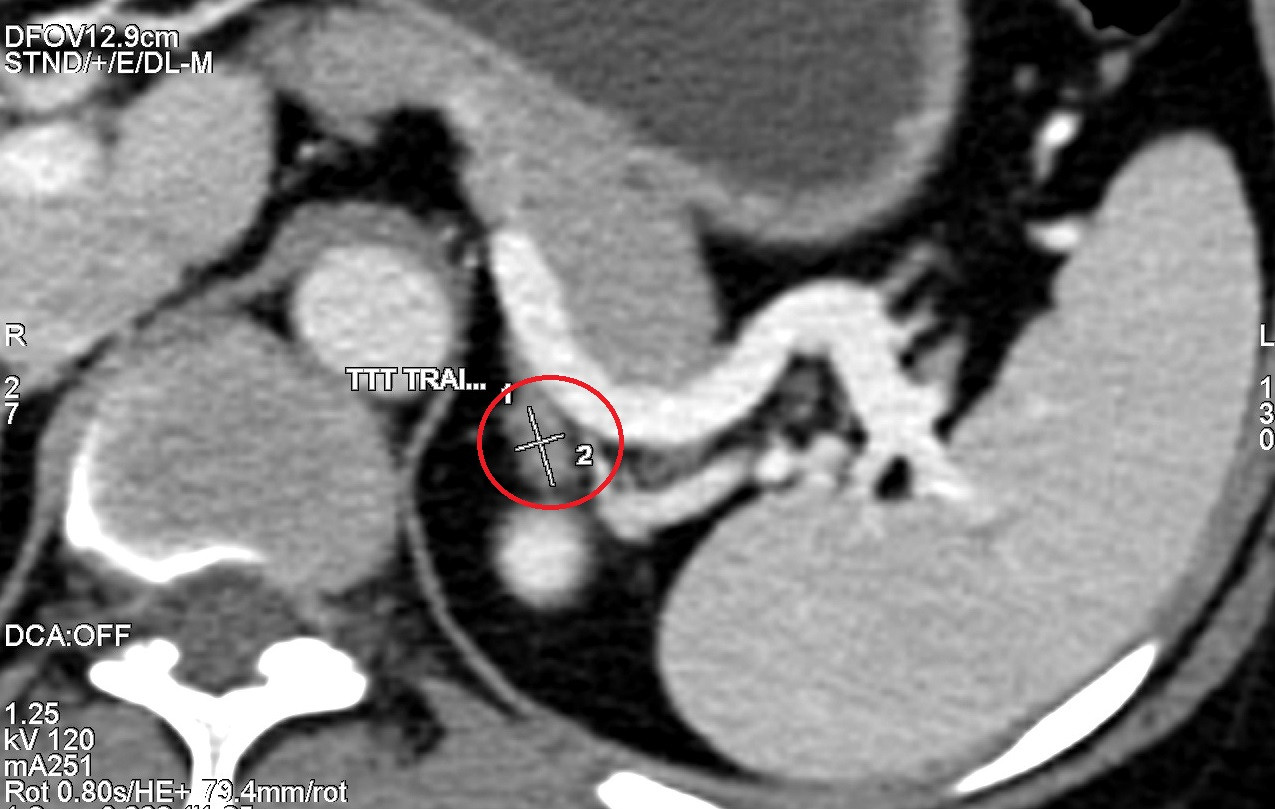

Đặc biệt, hình ảnh chụp CT phát hiện tuyến thượng thận trái bệnh nhân T có khối u kích thước 10mm, nghi ngờ mắc Adenoma tuyến thượng thận - bệnh lý hiếm gặp, là nguyên nhân chính của tình trạng cao huyết áp, suy tuyến thượng thận và bệnh addison.

| Hình ảnh chụp CT 2560 lát cắt phát hiện khối u tuyến thượng thận trái kích thước 10mm của bệnh nhân T |